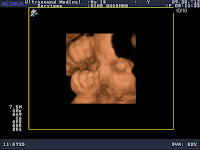

Sammy's 3D Ultrasound Pictures

34 weeks and 4 days

big ol' cheeks!

hand on mouth

rubbing my face

"no pictures, please!"

sucking his thumb

angry samurai face

more thumb sucking

"this thumb really tastes good!"

sticking his tongue out